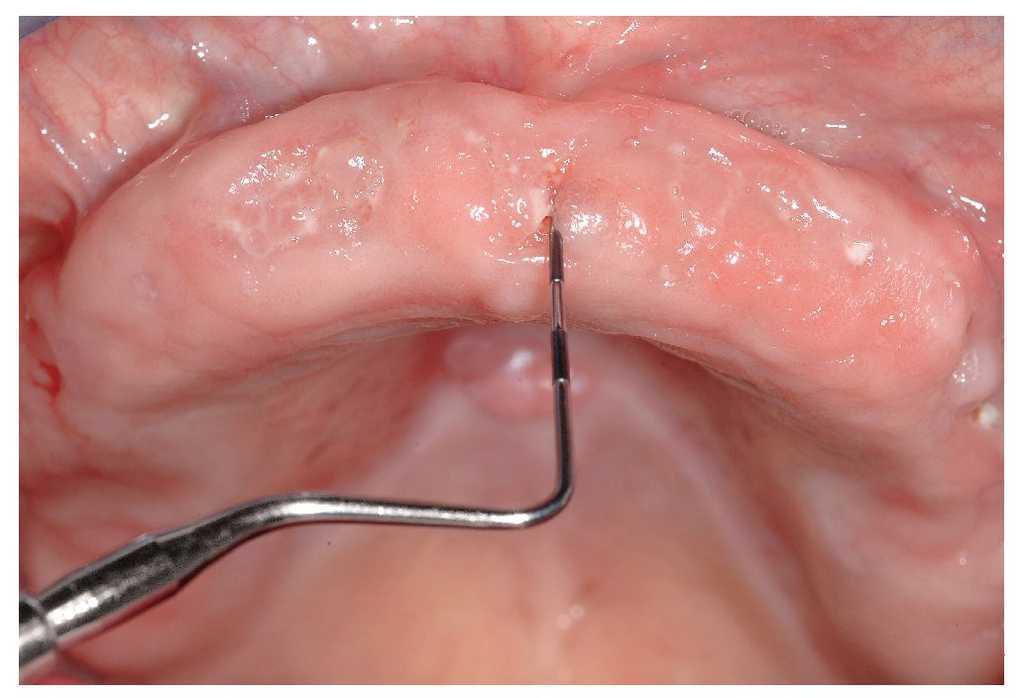

El signo clínico característico de la osteonecrosis asociada a bifosfonatos es un hueso de color blanco amarillento expuesto en el maxilar y/o en la mandíbula. El sondaje del hueso expuesto no suele provocar hemorragias y, por regla general, el paciente está asintomático22. No obstante, en áreas óseas extensas denudadas se pueden producir infecciones secundarias con un cuadro que incluye inflamación, producción de pus y dolor17. En pacientes dentados, la osteonecrosis imita a veces inicialmente un cuadro de periodontitis marginal. Después de la extracción, la cicatrización evoluciona de forma tórpida acompañada de una exposición ósea progresiva (figs. 1a a 1c). Una región afectada frecuentemente en la primera fase de la osteonecrosis asociada a bifosfonatos es la cortical lingual de la región de los terceros molares inferiores (figs. 2a y 2b). En los pacientes edéntulos se afectan a menudo zonas de la cresta alveolar maxilar y/o mandibular expuestas a la presión masticatoria directa de las prótesis totales (figs. 3a a 3c, 4a y 4b).

Figura 3c. En los antiguos alvéolos de las regiones 16/17 a 26/27 del maxilar se palpan zonas óseas expuestas con la sonda periodontal. La paciente no refiere molestias en el maxilar.